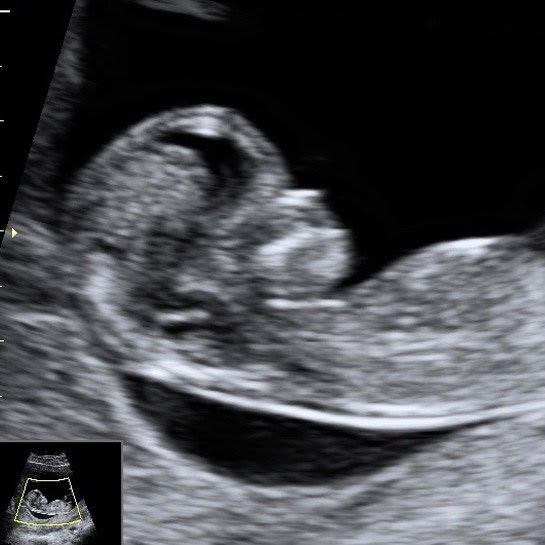

Examinare cu ultrasunete pe primul trimestru (săptămânile 11-14)